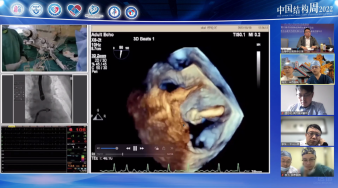

广东省人民医院罗建方教授团队带来一例二尖瓣机械瓣置换术后TAVR手术。由于该患者也存在三尖瓣关闭不全问题,但考虑到右心衰不严重,则优先处理主动脉狭窄问题。术后患者血流动力学稳定,舒张压64mmHg,无瓣周瘘问题。

74岁女性,反复呼吸困难8年,加重5年。合并1994年风湿性心脏瓣膜病机械瓣MVR(二尖瓣置换术),心房颤动,冠脉CTA提示冠状动脉粥样硬化。

超声描述:

主动脉瓣增厚,回声增强,瓣叶钙化,开放轻度受限,关闭不拢,主动脉瓣环内径21mm;

二尖瓣人工机械瓣,开放正常,瓣周未见异常回声;

尖瓣瓣尖增厚,开放好,关闭不拢;

双房明显扩大,室壁运动欠协调,收缩幅度尚好;

心包腔内未见液性暗区;

CDFI:二尖瓣人工瓣未见明显瓣周反流;

主动脉瓣反流,彩束面积72cm²,

三尖瓣反流,彩束面积13.7cm²,估测肺动脉收缩压53mmHg。

超声提示:

二尖瓣置换术后,人工机械瓣功能良好

主动脉瓣退变,重度主动脉瓣反流并中度狭窄

重度三尖瓣反流,中度肺高压